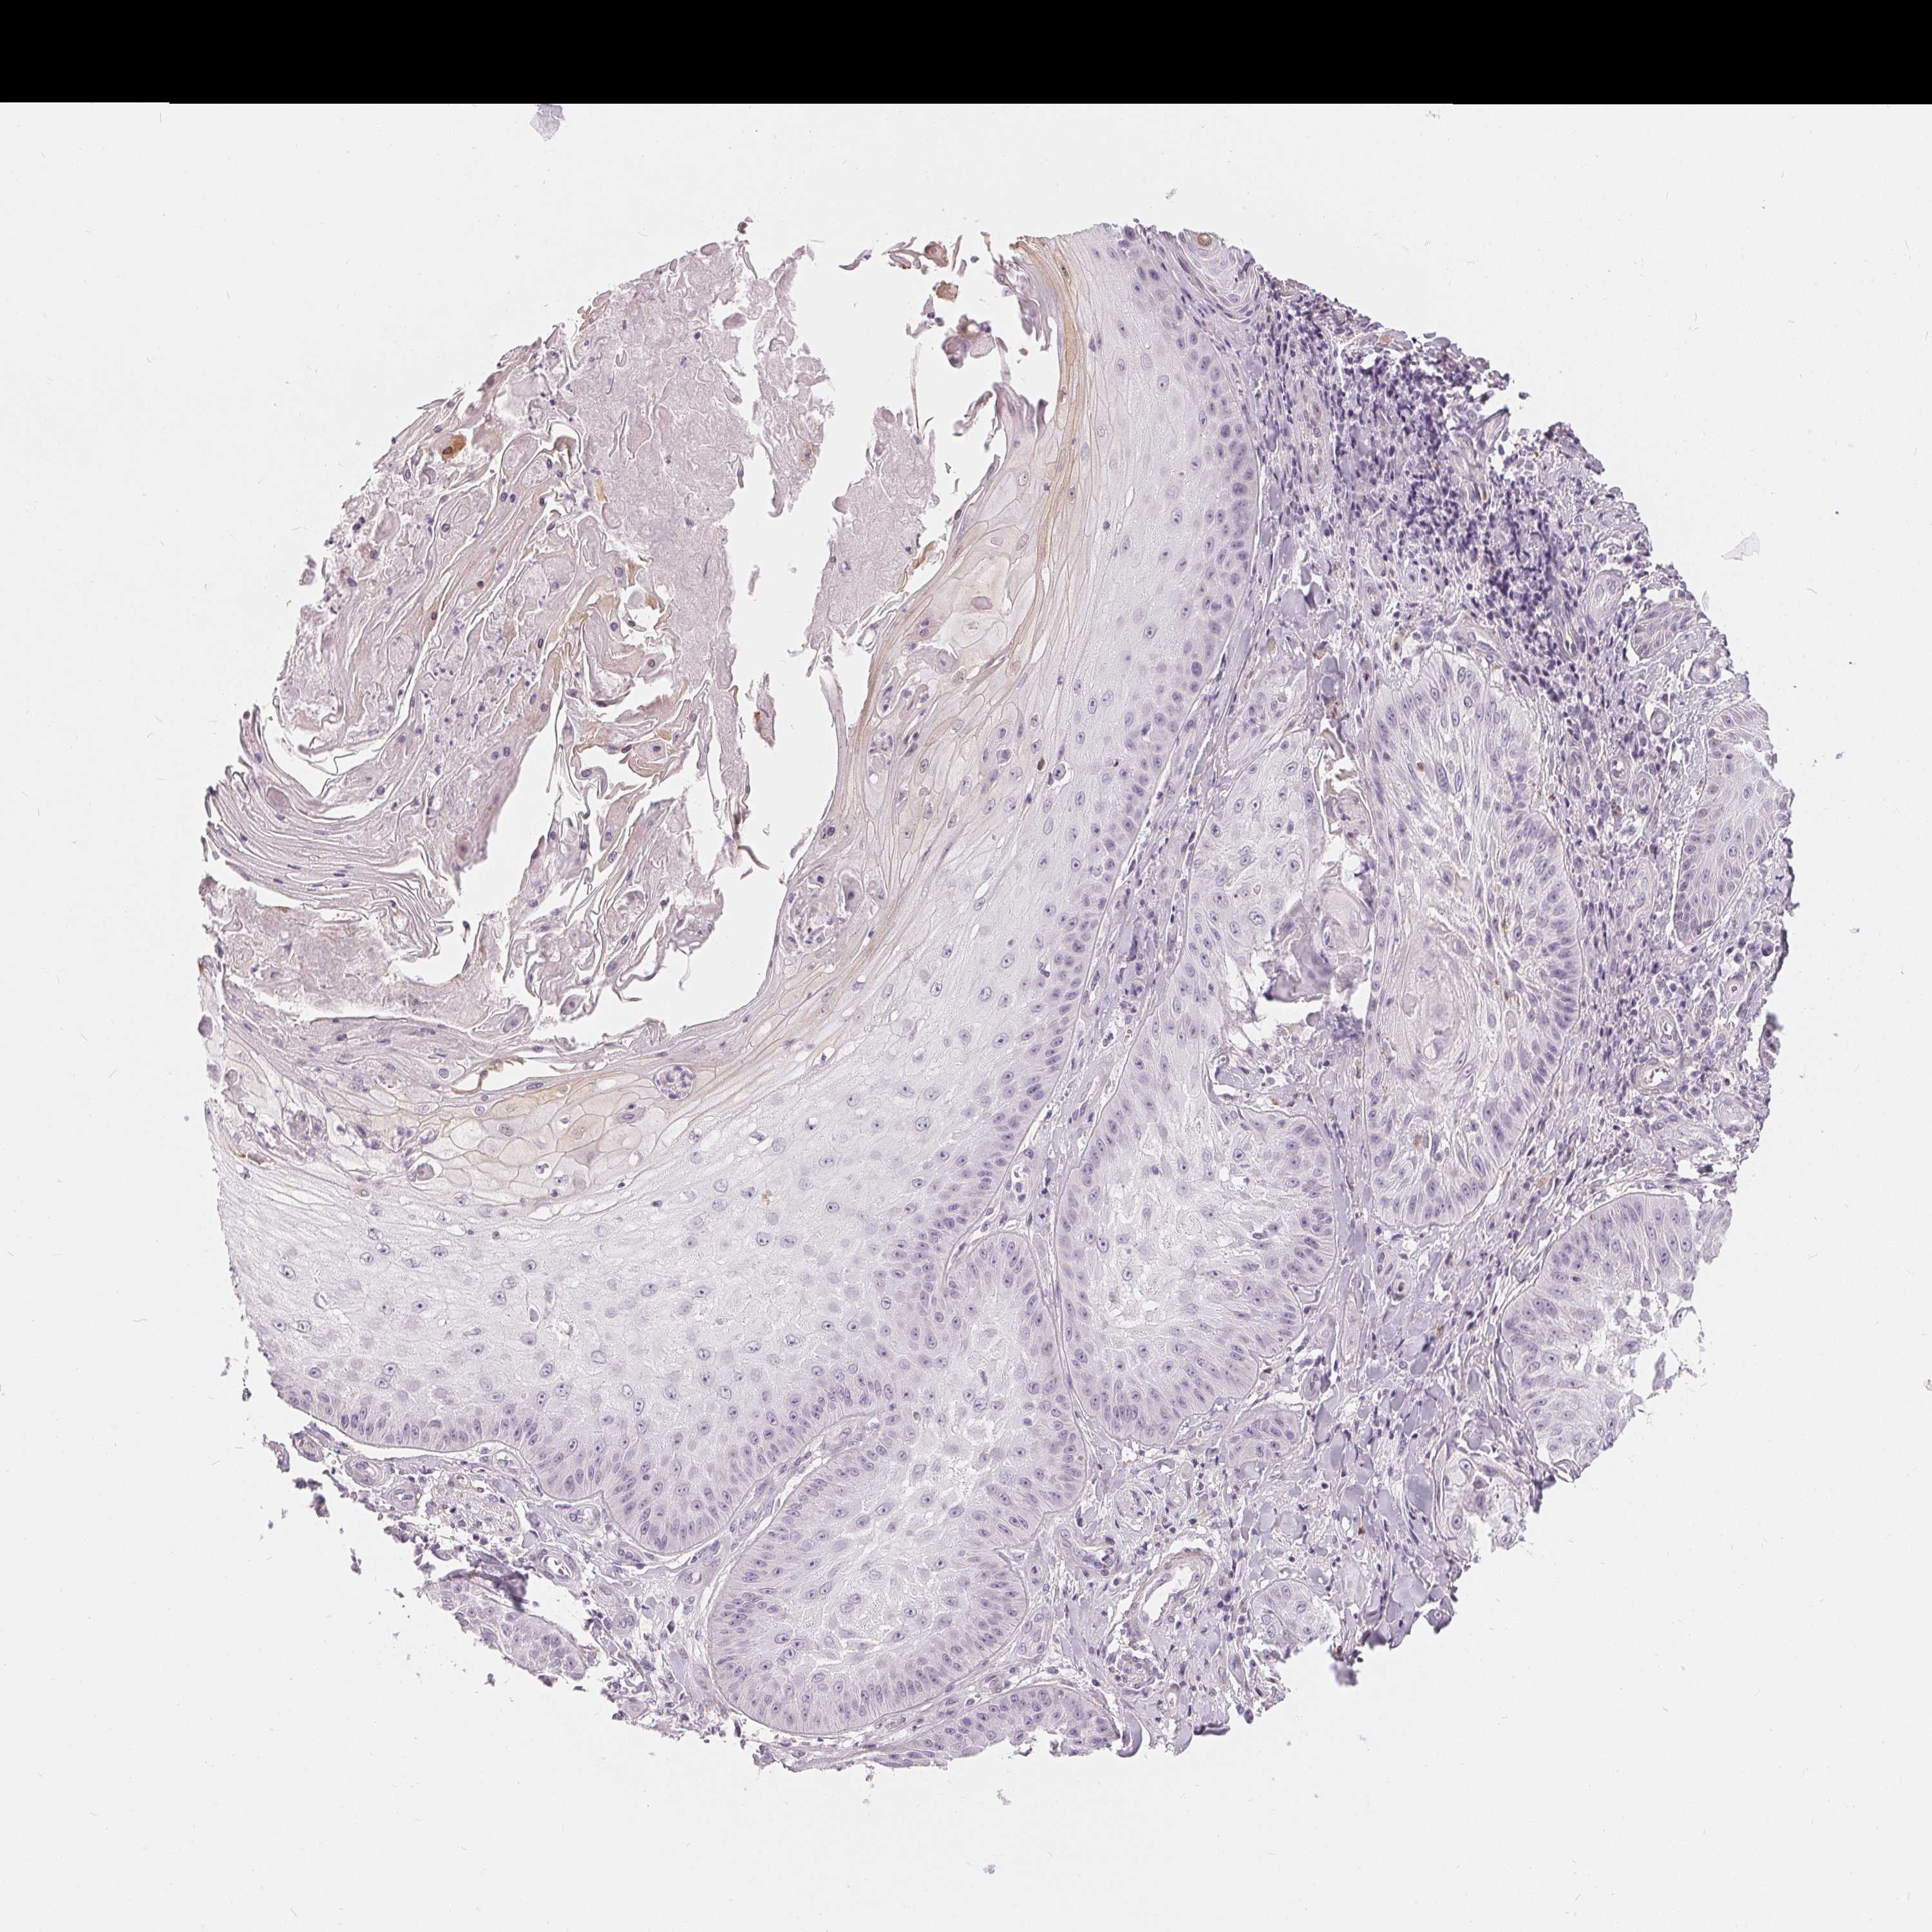

SKIN CANCER - Protein expressioni

A mouse-over function shows sample information and annotation data. Click on an image to view it in a full screen mode. Samples can be filtered based on level of antibody staining by selecting one or several of the following categories: high, medium, low and not detected. The assay and annotation is described here.

Antibody stainingi

Antibody staining in the annotated cell types in the current human tissue is reported as not detected, low, medium, or high, based on conventional immunohistochemistry profiling in selected tissues. This score is based on the combination of the staining intensity and fraction of stained cells.

Each image is clickable and will lead to virtual microscopy that enables deeper exploration of all samples and also displays staining intensity scores, fraction scores and subcellular localization as well as patient and tissue information for each sample.

Antibody HPA030180

Antibody CAB018632

Staining

Basal cell carcinoma

Squamous cell carcinoma, NOS